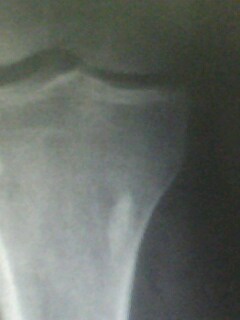

以下是引用muzi888在2010-5-12 11:02:00的发言:[br]骨岛,髁间棘及胫骨关节面有骨增生改变,余无异常。

以下是引用随光逐影在2010-5-12 14:43:00的发言:[br]1)胫骨上段骨岛。2)膝关节退行性改变。